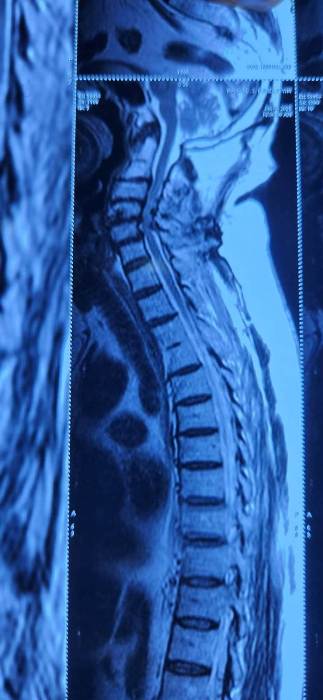

Mumbai, July 10, 2025: 71-year-old male patient from Malad (Mumbai) underwent a successful posterior cervical laminectomy for multilevel cervical spondylotic myelopathy at Apex Hospital, Borivali which is part of Apex group of Hospitals last week. The surgery marked another important milestone in the hospital’s commitment to advanced spine care. The patient had been experiencing gait instability, weak hand grip, difficulty with fine motor tasks like buttoning his shirt, and radiating pain in both upper limbs—classic symptoms of cervical myelopathy, a condition caused by compression of the spinal cord in the neck due to age-related degenerative changes. If left untreated, this condition can progressively impair mobility and hand function, significantly diminishing quality of life.

Following a comprehensive clinical evaluation and imaging, the diagnosis of multilevel cervical myelopathy was confirmed. The surgical team opted for a posterior cervical laminectomy, a procedure designed to relieve pressure on the spinal cord by removing the compressive bony structures. The surgery was performed by Dr. Umang Sheth and Dr. Meet Shah, Spine Surgeons at Apex Hospital, Borivali. The procedure lasted 2 hours and 15 minutes, with minimal blood loss (approx. 100 ml) and no intraoperative complications, ensuring a smooth and safe operative course.